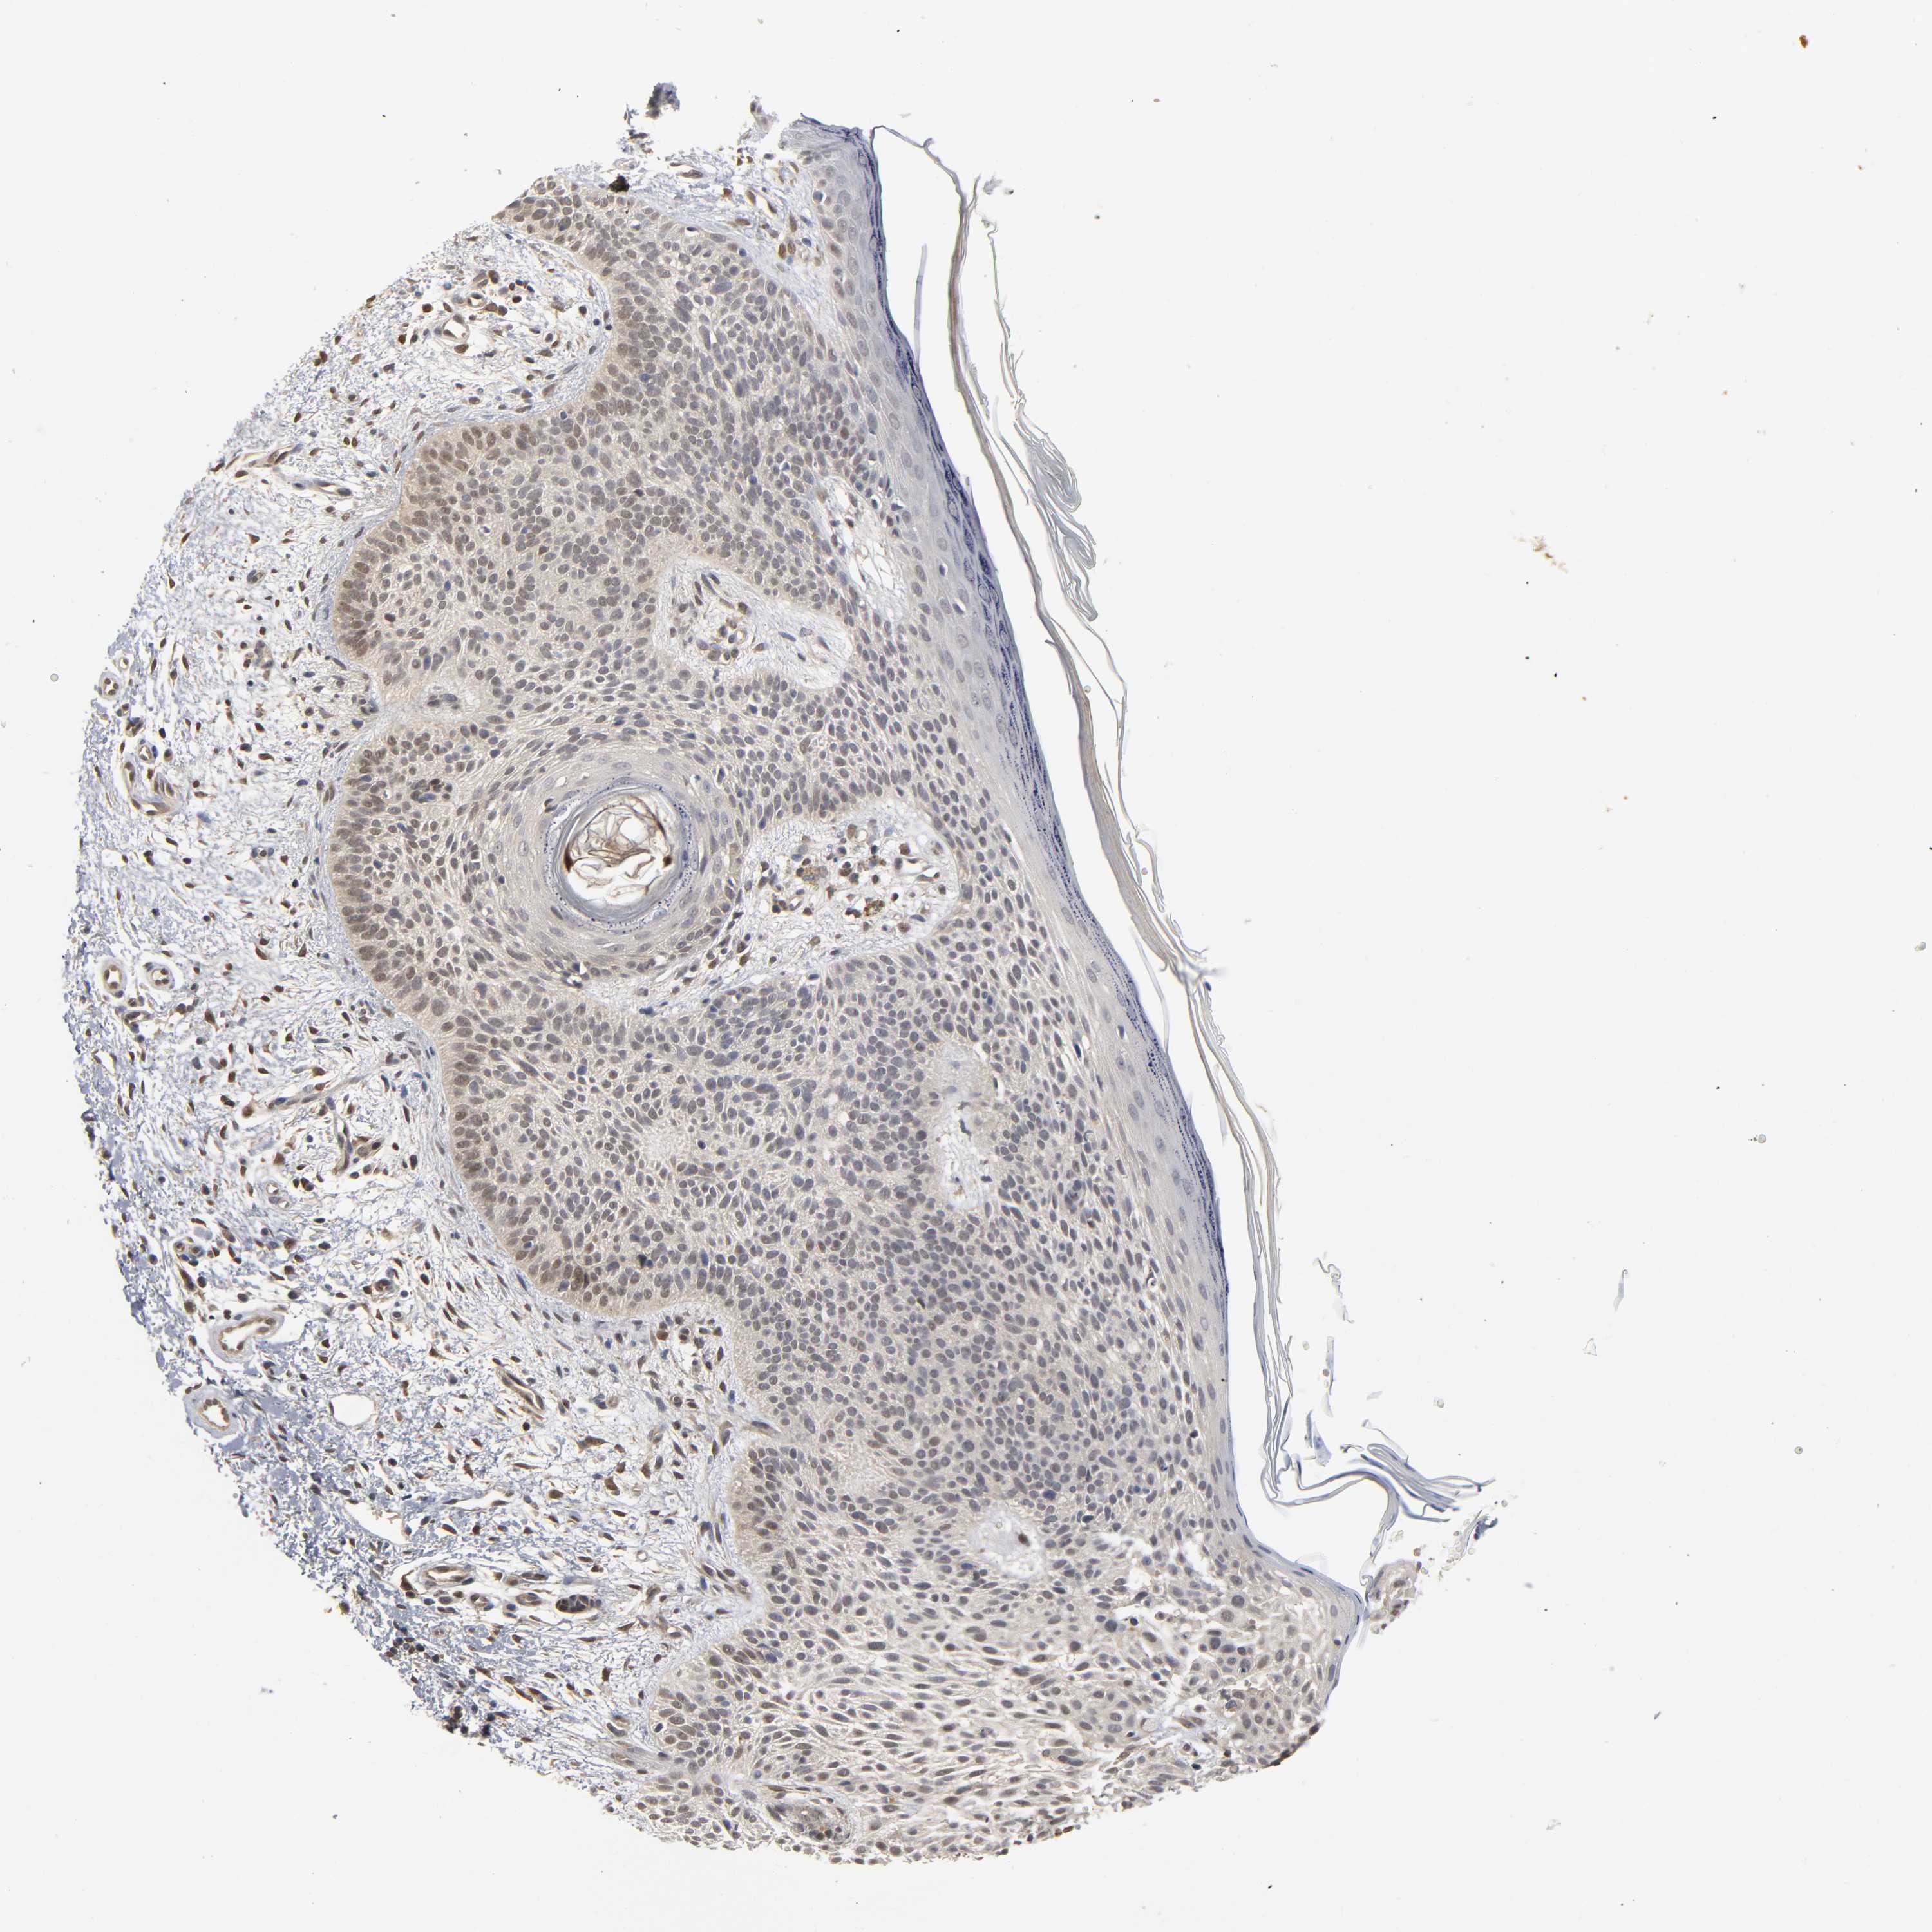

Basal cell and squamous cell cancer

SKIN CANCER - Protein expressioni

A mouse-over function shows sample information and annotation data. Click on an image to view it in a full screen mode. Samples can be filtered based on level of antibody staining by selecting one or several of the following categories: high, medium, low and not detected. The assay and annotation is described here.

Antibody stainingi

Antibody staining in the annotated cell types in the current human tissue is reported as not detected, low, medium, or high, based on conventional immunohistochemistry profiling in selected tissues. This score is based on the combination of the staining intensity and fraction of stained cells.

Each image is clickable and will lead to virtual microscopy that enables deeper exploration of all samples and also displays staining intensity scores, fraction scores and subcellular localization as well as patient and tissue information for each sample.

Antibody HPA004190

Squamous cell carcinoma, NOS

Basal cell carcinoma